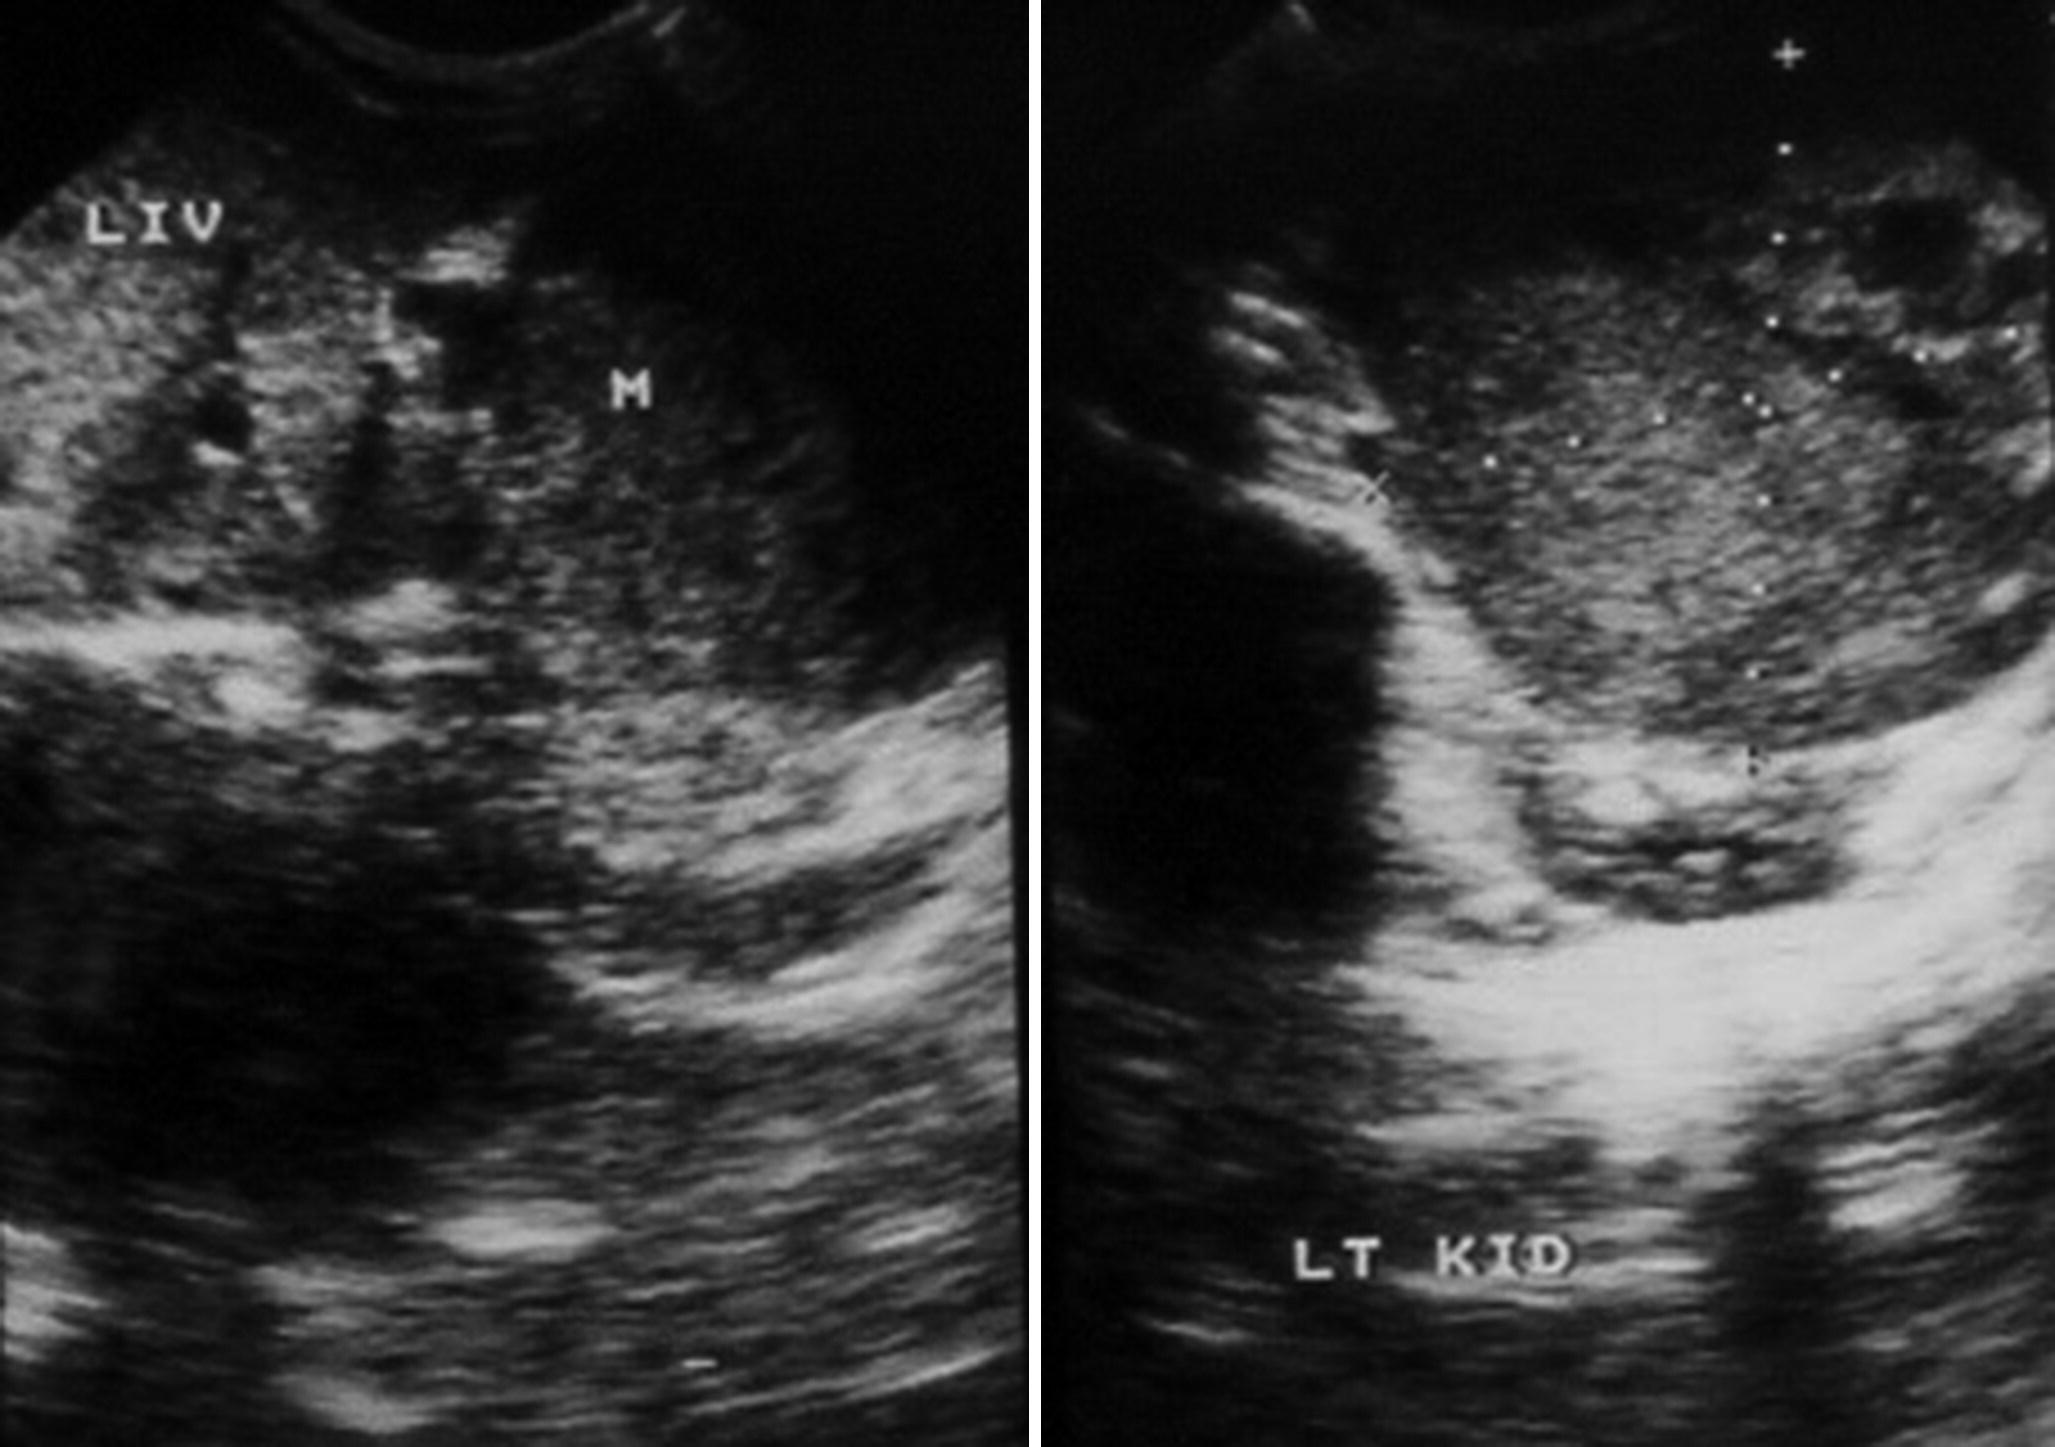

Pdf Cellular Congenital Mesoblastic Nephroma With Contralateral Medullary Nephrocalcinosis